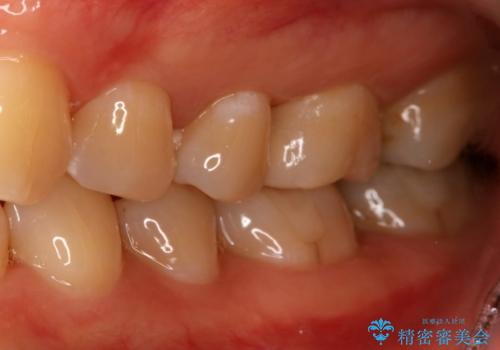

奥歯を白くしたい

- 左上6番の銀歯をセラミックにしたいと希望され来院された患者様です。

切削量を考慮し、セラミックインレーを選択しました。

銀歯を除去したところ虫歯が深かったので、CRを詰めた上で形態を整えています。